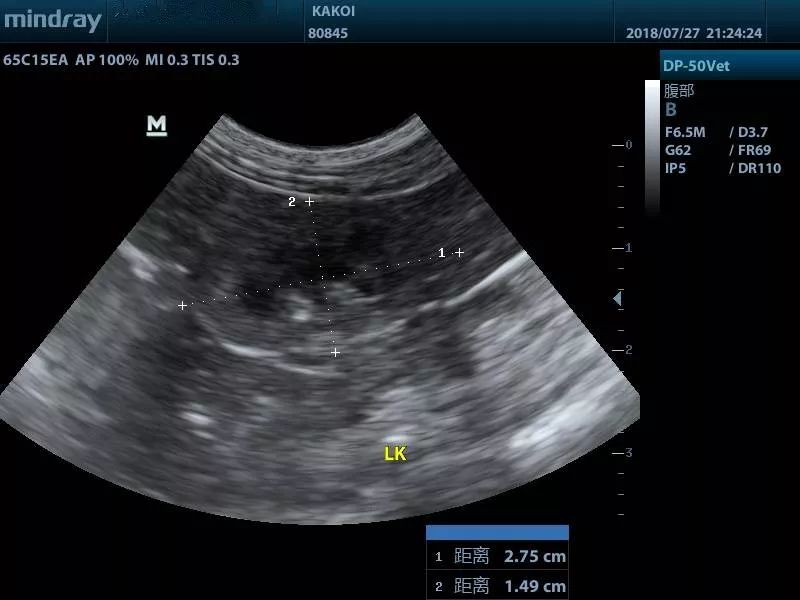

图为猫肾萎缩